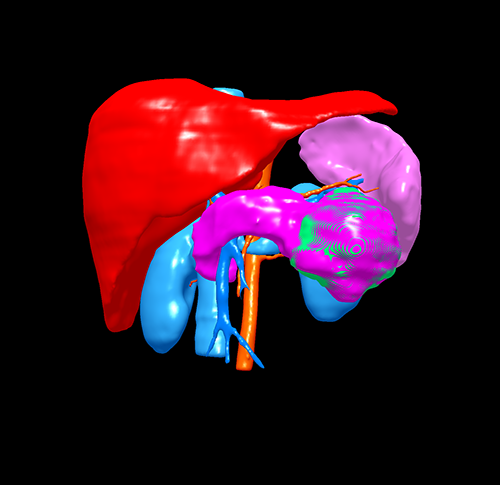

胰体尾实性假乳头状瘤---腹腔镜胰体脾切除